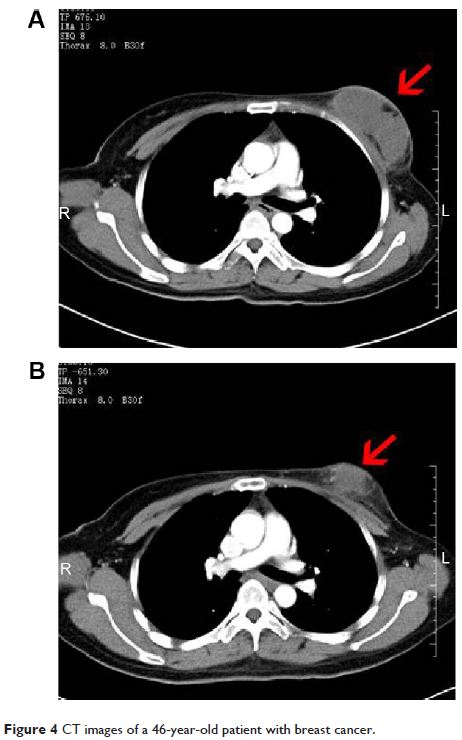

Original Research

- 作者:Shuzhen Liang, Kecheng Xu, Lizhi Niu, Xiaohua Wang, Yingqing Liang, Mingjie Zhang, Jibing Chen, Mao Lin

- 期刊:OncoTargets and Therapy